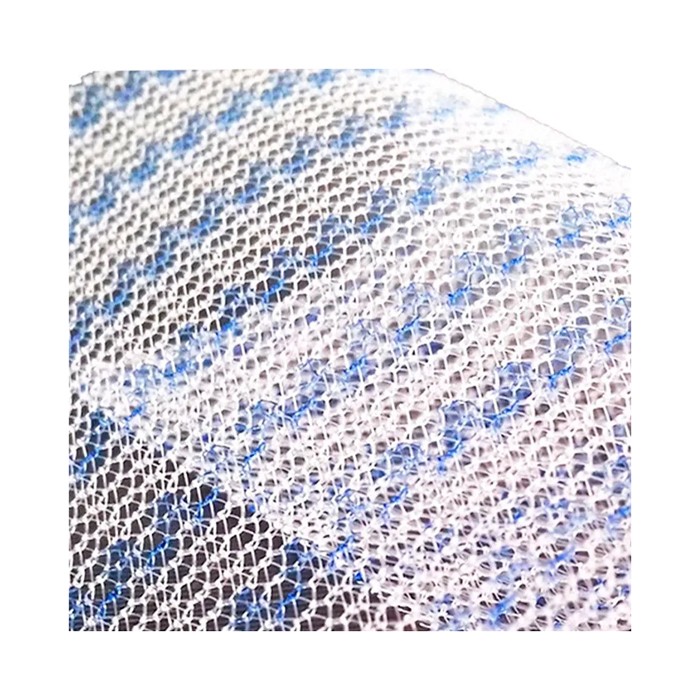

- Макропористая структура. Крупные поры (более 1 мм) позволяют тканям организма свободно прорастать сквозь сетку, формируя прочный соединительнотканный каркас и снижая риск хронического воспаления, серомы или отторжения.

| Тип плетения / структура | Макропористая, монофиламентная |

| Цвет | Белый, синий (может варьироваться в зависимости от партии) |